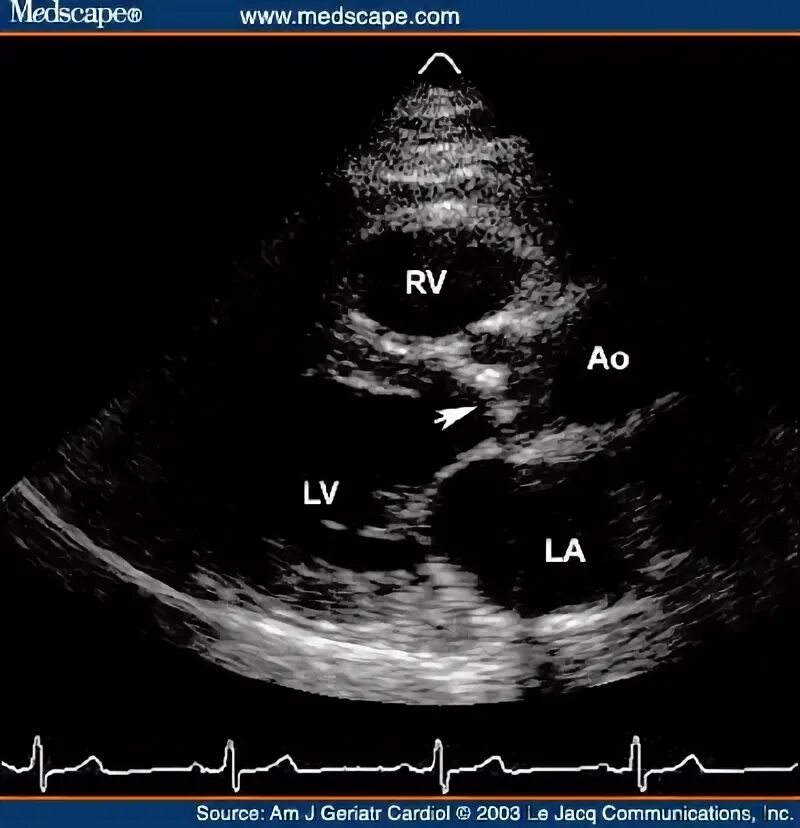

Уплотнение стенок аорты сердца на узи что